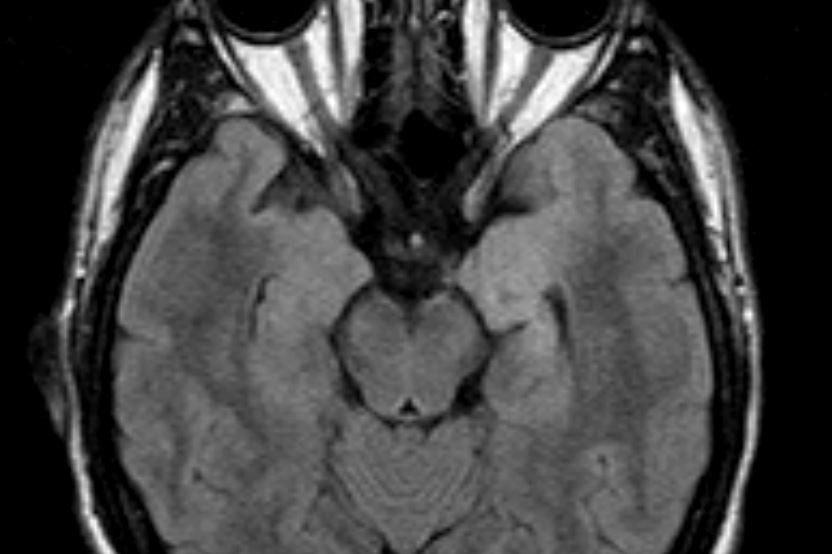

Ασθενής άνδρας, 52 ετών με κώφωση αριστερά και ιλιγγική συνδρομή. Η μαγνητική τομογραφία εγκεφάλου ανέδειξε χωροκατακτητική εξεργασία στην αριστερή γεφυροπαρεγκεφαλιδική…